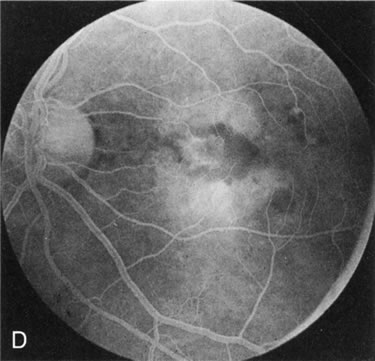

FA plays an important role in the understanding of this rare disorder. In the earliest manifestations of the disease, FA shows a single, isolated choroidal neovascular membrane unassociated with other causes of a membrane, such as drusen or angioid streaks (Fig. 13).25 Presumably this membrane is the cause of the subsequent hemorrhagic maculopathy with secondary disciform scarring, occurring initially in the macula but often extending throughout the retina.

Fig. 13. Hereditary hemorrhagic macular dystrophy (pseudoinflammatory macular dystrophy of Sorsby). Fluorescein angiography in this family member demonstrates that the earliest finding is an isolated choroidal neovascular membrane B). Despite laser photocoagulation, a hemorrhagic maculopathy developed in this eye (C, D) and eventually a disciform scar (E) formed, as it had in the fellow eye, and in the eyes of other affected family members.

Abnormal choroidal perfusion, manifested on FA as a delay in choriocapillaris filling, has been seen in the restudy of some of Sorsby's initial pedigrees.26 This unusual pattern has been related to the histopathologic finding of a “confluent, lipid-containing, amorphous deposit found between the basement membrane of the RPE and the inner collagenous layer of Bruch's membrane.”27